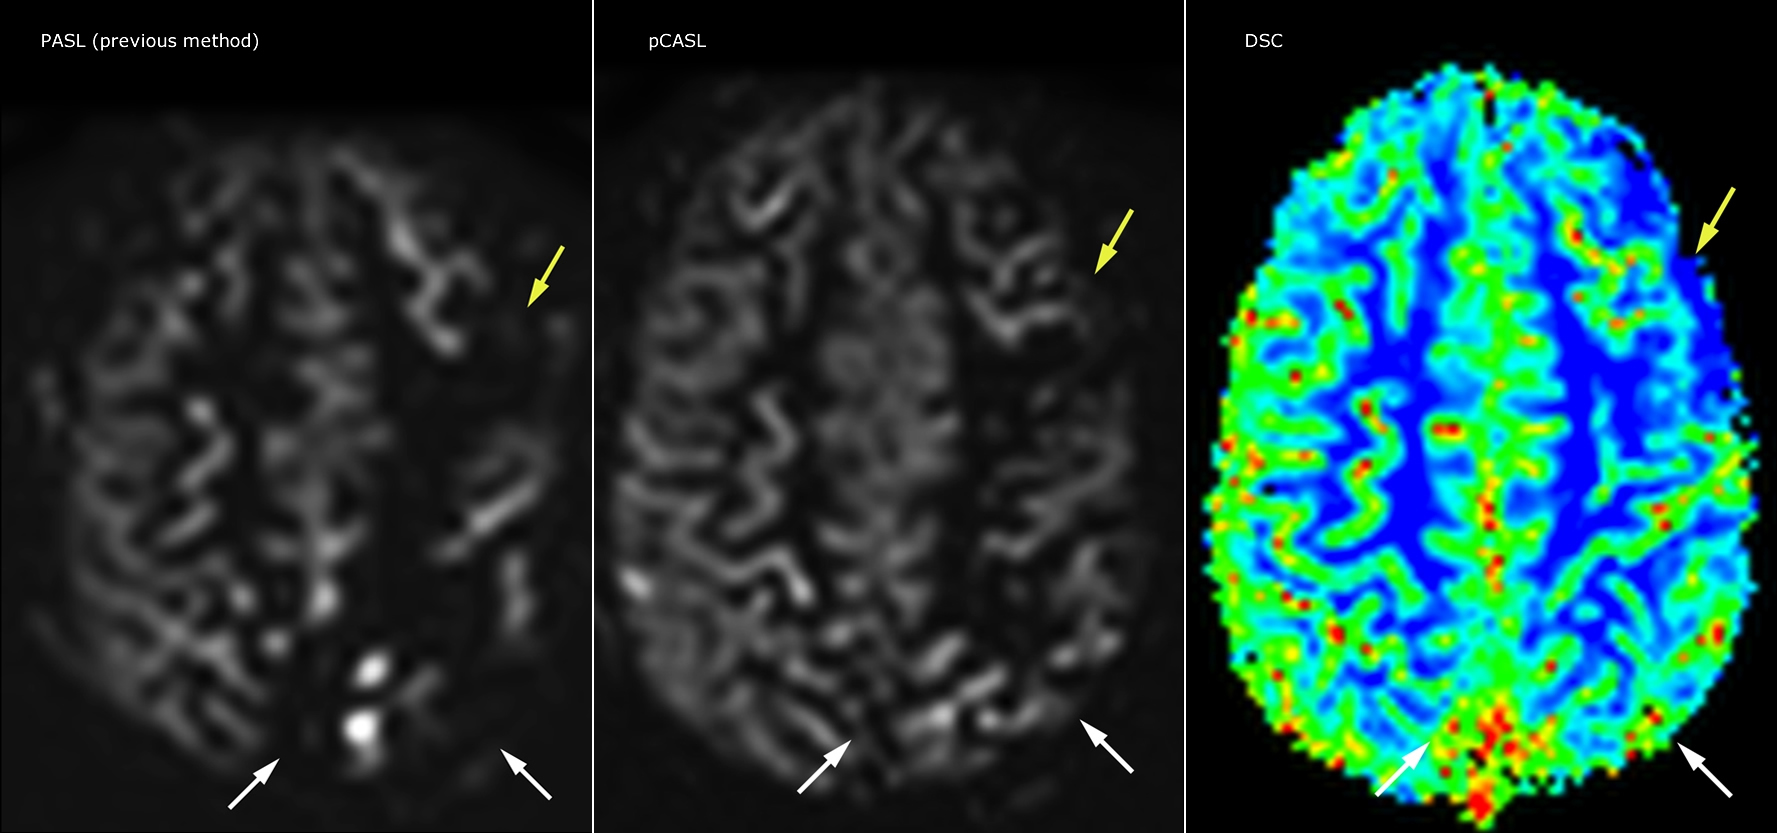

pCASL helps assess brain perfusion without contrast

Pseudo-continuous arterial spin labeling (pCASL) was developed for brain perfusion imaging without contrast agent. “This is very desirable in pediatric patients where the general trend is to limit the administration of contrast,” says Dr. Miller.

Dr. Miller uses pCASL for all patients who present with chronic and acute cerebrovascular abnormalities such as acute stroke, as well as patients who present with signs of acute inflammation in the brain, and occasionally in patients with tumors, to assess the perfusion status of their tumor.

“In combination with diffusion weighted imaging, it can help give a more extended assessment of the degree of perfusion abnormality in a patient who is suffering acute ischemia. We have a number of patients who have chronic arterial insufficiency due to prior arterial abnormalities or acquired arterial abnormalities such as sickle cell disease or neurofibromatosis. Sometimes the child’s first manifestation of disease progression is a reduction in brain perfusion before stroke symptoms manifest clinically or in diffusion weighted imaging. We use pCASL to help delineate the perfusion abnormality.”

Growing confidence in specific applications

“We built up confidence in pCASL by comparing it to contrast-based perfusion imaging. Once we had confidence that it was representing what the contrast perfusions were representing, we increased our diagnostic confidence by serial imaging in either the acute stage or the long term stages in a number of patients with arterial abnormalities.

To other new users I would recommend to also start to interpret the pCASL images in comparison with other standard imaging – T2 and FLAIR and DWI – until the user gains confidence in interpreting these images by themselves.”

“A powerful use of pCASL is in patients with chronic cerebrovascular stenosis, where clinicians desire information on how compensatory mechanisms of the brain are performing to enable perfusion to the brain. Often clinicians take into account how the compensatory mechanisms appear to help to provide adequate perfusion to the patient’s brain, and they may intervene surgically or make some other management decision.”

“Another special application is the assessment of cerebrovascular reactivity with a Diamox perfusion exam, where we subtract two sets of pCASL images.”

Efficiencies gained with pCASL

“pCASL has now become more of a first-line scan for assessing perfusion for us, as opposed to DSC-based perfusion imaging with contrast agent. And in patients who were not planned to have contrast, we can perform pCASL for perfusion imaging without need to stop the exam, pull the patient out, and put in an IV. It also negates the postprocessing that’s necessary for dynamic susceptibility contrasts. And it allows us to repeat perfusion imaging in the same patient at the same imaging time, which is helpful in terms of patient motion, or in a situation where a scan needs to be done before pharmacological perfusion imaging.”